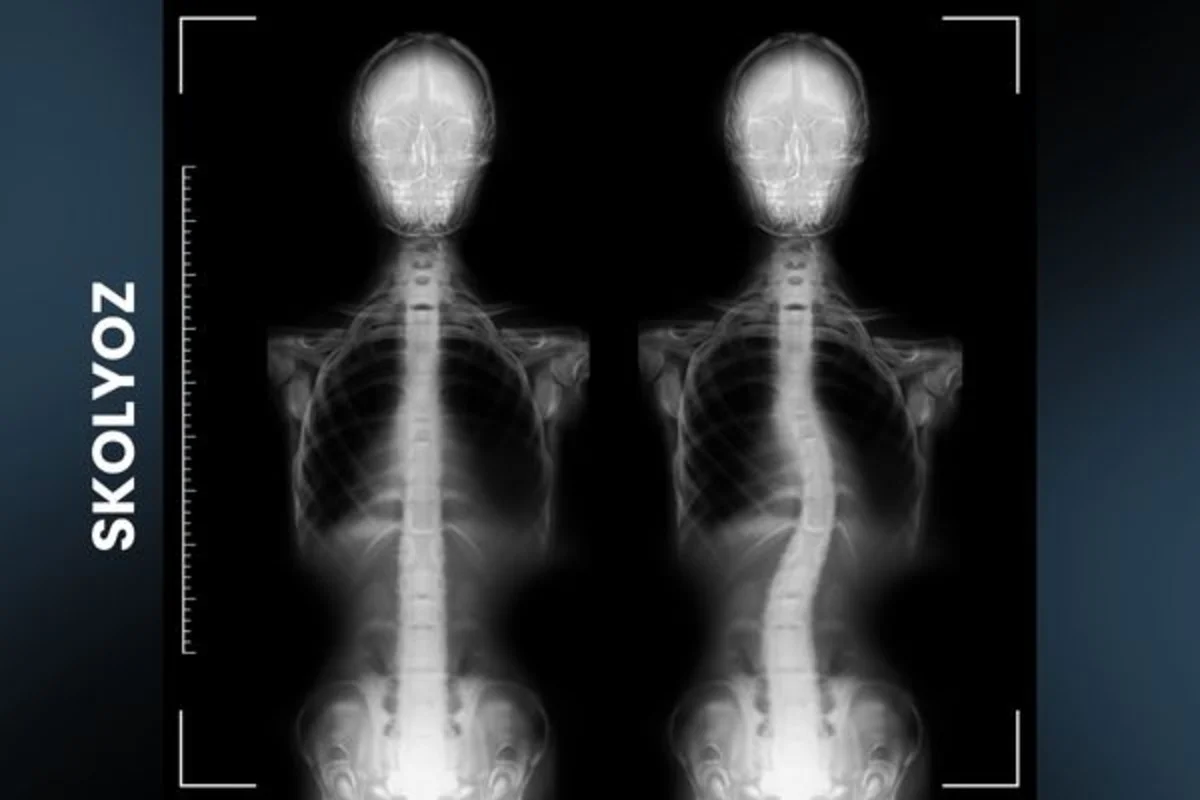

Skolyoz (Omurga Eğriliği) Erken Teşhisin Önemi

Skolyoz, omurgada görülen eğriliktir ve erken teşhis, tedavi başarısı için kritik öneme sahiptir. Bu yazıda skolyozun be...